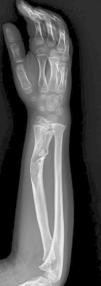

Se realizó una RM de antebrazo (fig. 3) donde se observaron infiltrados condrales de arquitectura lobular con calcificaciones de baja intensidad. La biopsia percutánea de radio confirmó el diagnóstico de encondromatosis múltiple o enfermedad de Ollier.